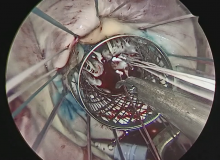

The left atrium was opened, the atrial lift retractor was inserted, and the valve was exposed. Ring stitches were placed. The valve was tested, and the ruptured chord in the posterior segment can be seen in the video. Methylene blue was used to mark the valve to find where the area of coaptation should have been. The sizing of the chordae in the case of the Leipzig loop technique was performed, just to illustrate. The valve was found to have only a posterior segment flail. The Superflex retractor was used to expose the papillary muscles. The neochords were sutured to the papillary muscle heads to the posteromedial muscle. Each one of these chords was anchored to the posterior segment flail with a figure-of-eight locking stitch, using each arm of the chordal system. With this, one stitch is applied and locked, and the sister arm is applied close to this—approximately 1 mm apart—and locked. This process was applied for each of the chordae. Notice that the leaflet was kept in a flail position above the annular plane because it is easier to push down the leaflet than to pull it up once the suture is locked.

The valve was tested, and one can see that the area of coaptation is improved and there was no longer a flail. Fine-tuning of the height of the posterior leaflet can be performed by grasping the posterior segment and with one hand grasping the suture. The authors did like the height of the posterior leaflet, so the sutures were tied. The valve was tested, and a 34 mm complete annular ring was used. Postoperative echocardiography showed a mean gradient of 3 mm Hg and no residual mitral regurgitation. The patient was discharged home on postoperative day number four.